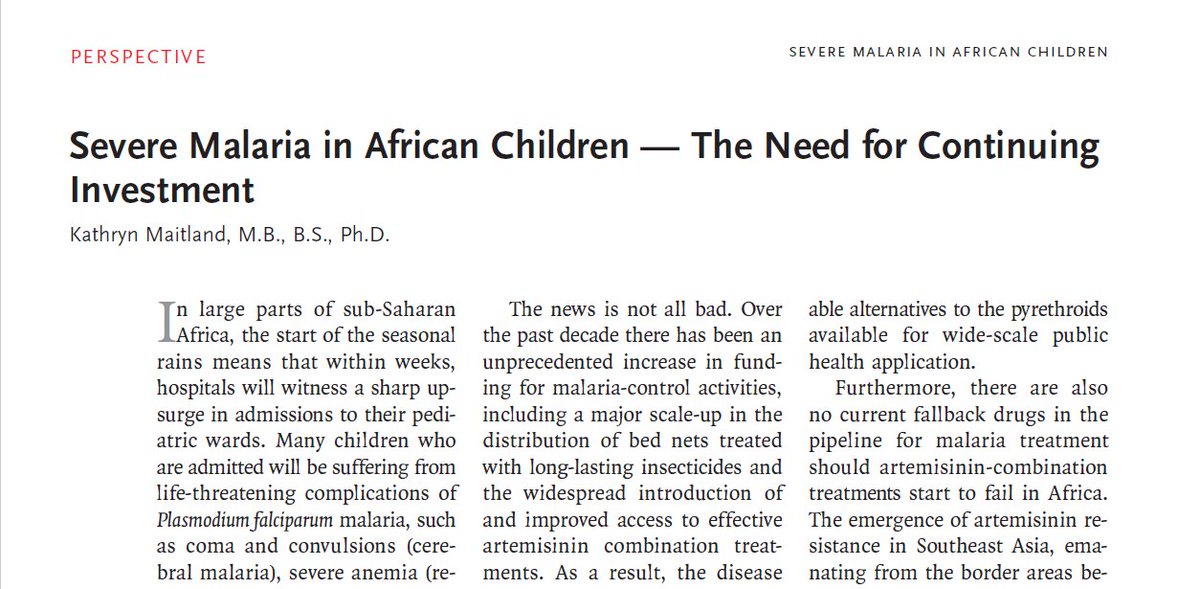

Perspective: Severe Malaria in African Children — The Need for Continuing Investment http://nej.md/2gZTUfz pic.twitter.com/jnslMy8MGl